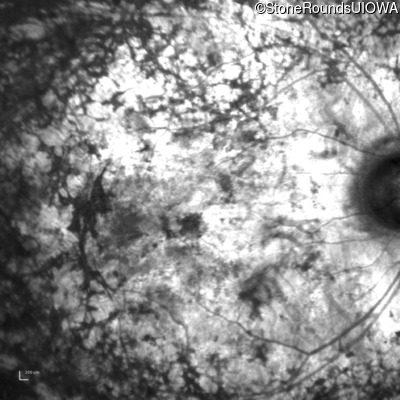

Infrared Fundus Photograph - Right - Light Perception

Exemplar